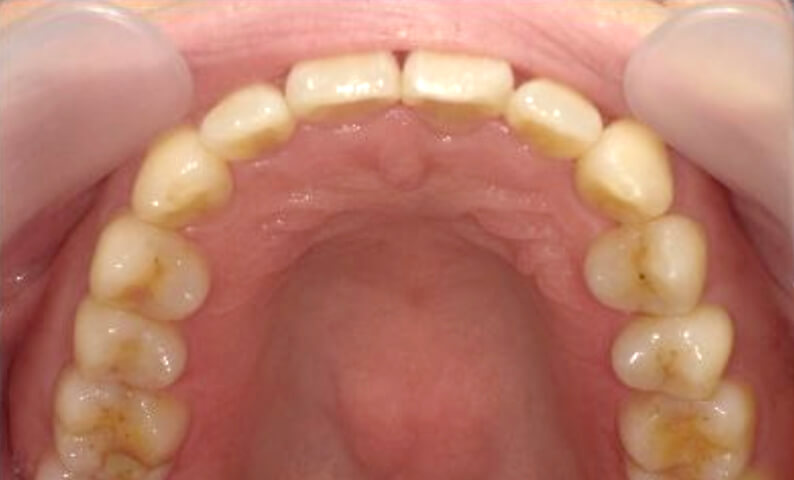

症例_002 下顎だけの部分矯正

治療期間:6ヶ月金額:21万円+税女性前歯のデコボコ下の前歯だけ

| Before | After |

|---|---|

|